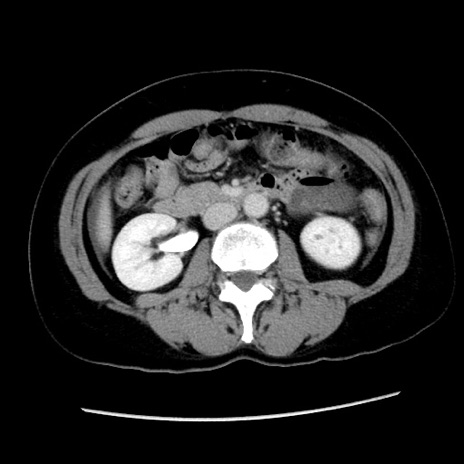

症例10(横断像)

【症例】 50歳代女性

【主訴】 腹痛

【現病歴】前日生レバーを食べた。今朝に排便あり。 昼前に突然発症の腹痛を生じ、当院救急外来を受診した。

【既往歴】 子宮筋腫にてで子宮全摘後

【身体所見】 意識清明、腹部:平坦、軟、下腹部やや左を中心に圧痛・反跳痛あり、筋性防御あり

【データ】WBC 7800、CRP 0.07